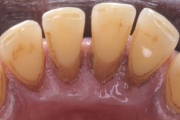

- igemepiir on taandunud (3)

- hamba kinnitussidemete kadu (3)

- igemepealne hambakivi (5)

- igemealune hambakivi (4)

- hammaste tundlikkus (9)